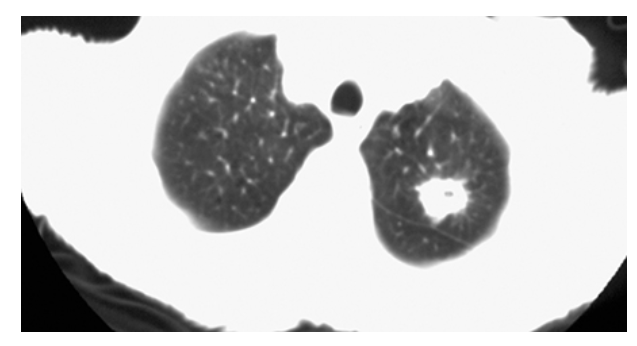

Carcinoma of the Lung. CT of the chest with lung windows demonstrates a round mass with irregular speculated margins in the left upper lobe.